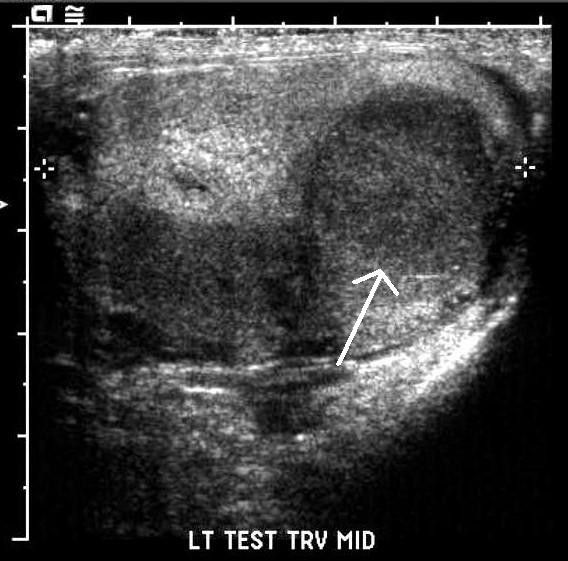

海口市人民医院的检查报告显示王义左侧睾丸附睾炎扭转.

睾丸微石症